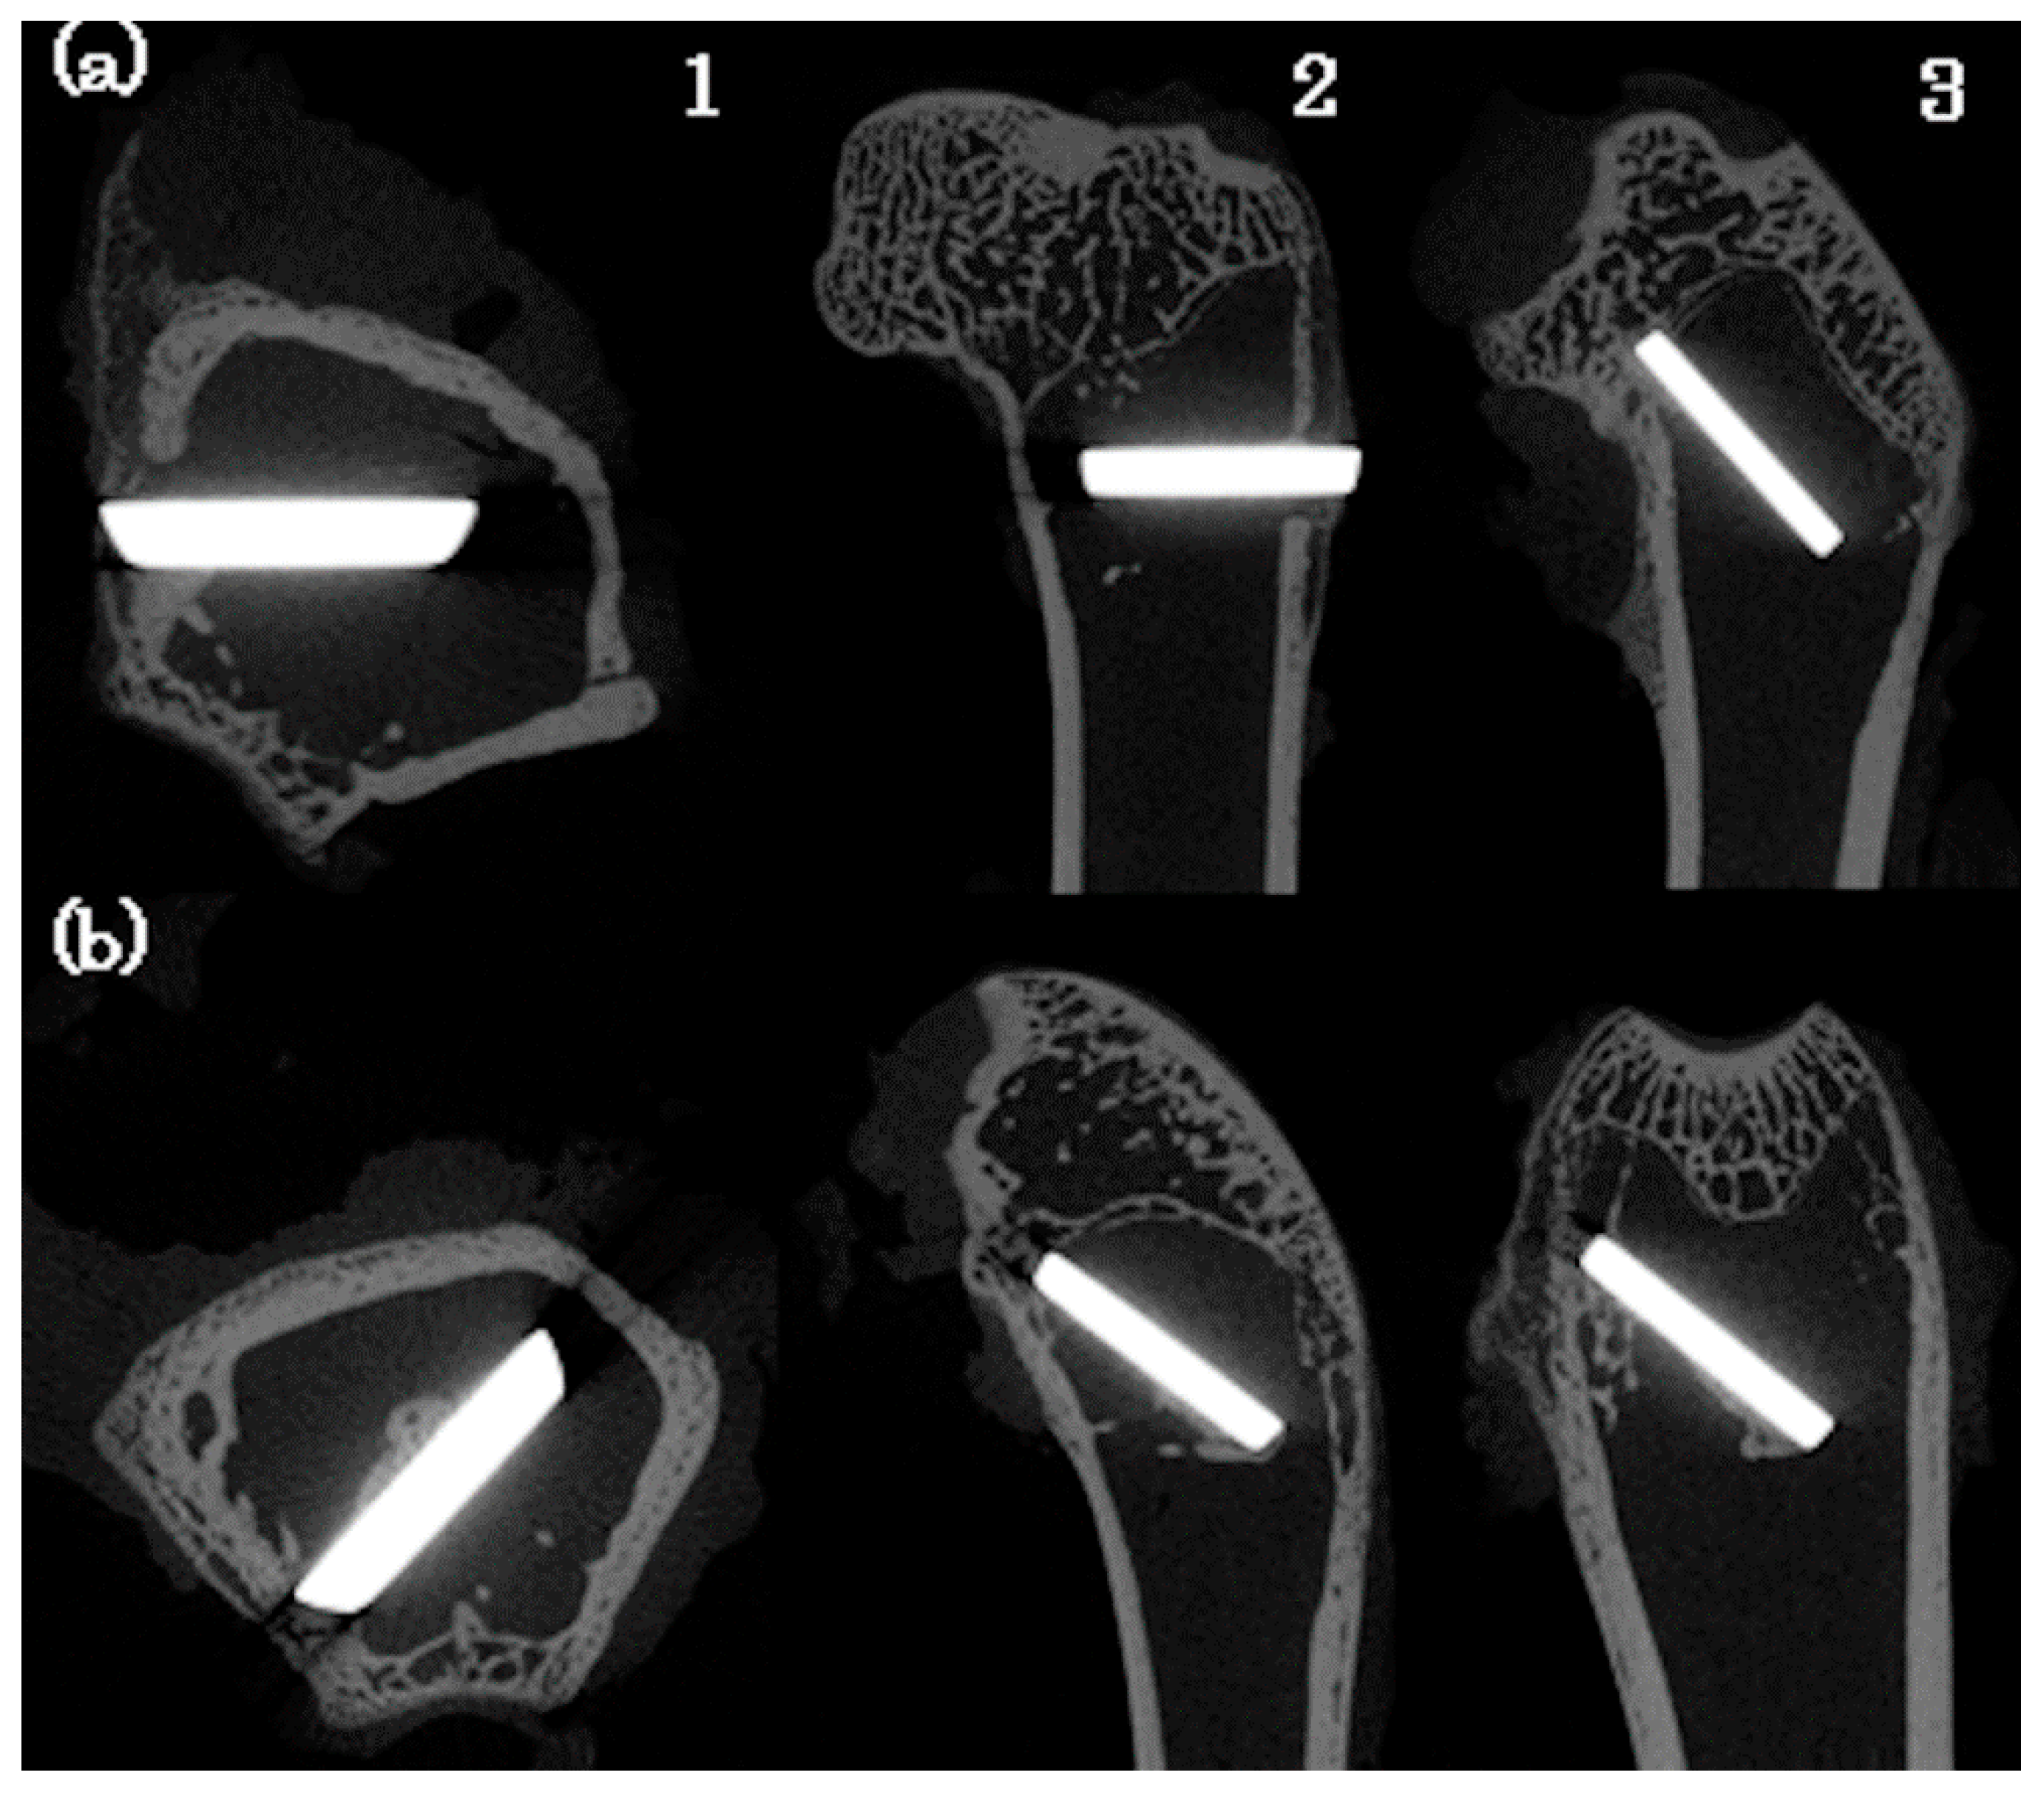

3.6. Animal Experiment

On micro CT, active new bone formation was noted around the Ti disk on the bone marrow side in the S-100 group compared with that in the Control group (Figure 10). On Villanueva bone staining, many osteoid fragments stained red purple were noted on the bone marrow side of the disk in the S-100 group compared with that in the Control group (Figure 11). In addition, the BIC value was significantly higher in the S-100 group than in the Control group (Figure 12).

Figure 10. Micro CT of rabbit femur. (a) Control, (b) S-100. 1: X–Y plane, 2: Y–Z plane, 3: Z–X plane.